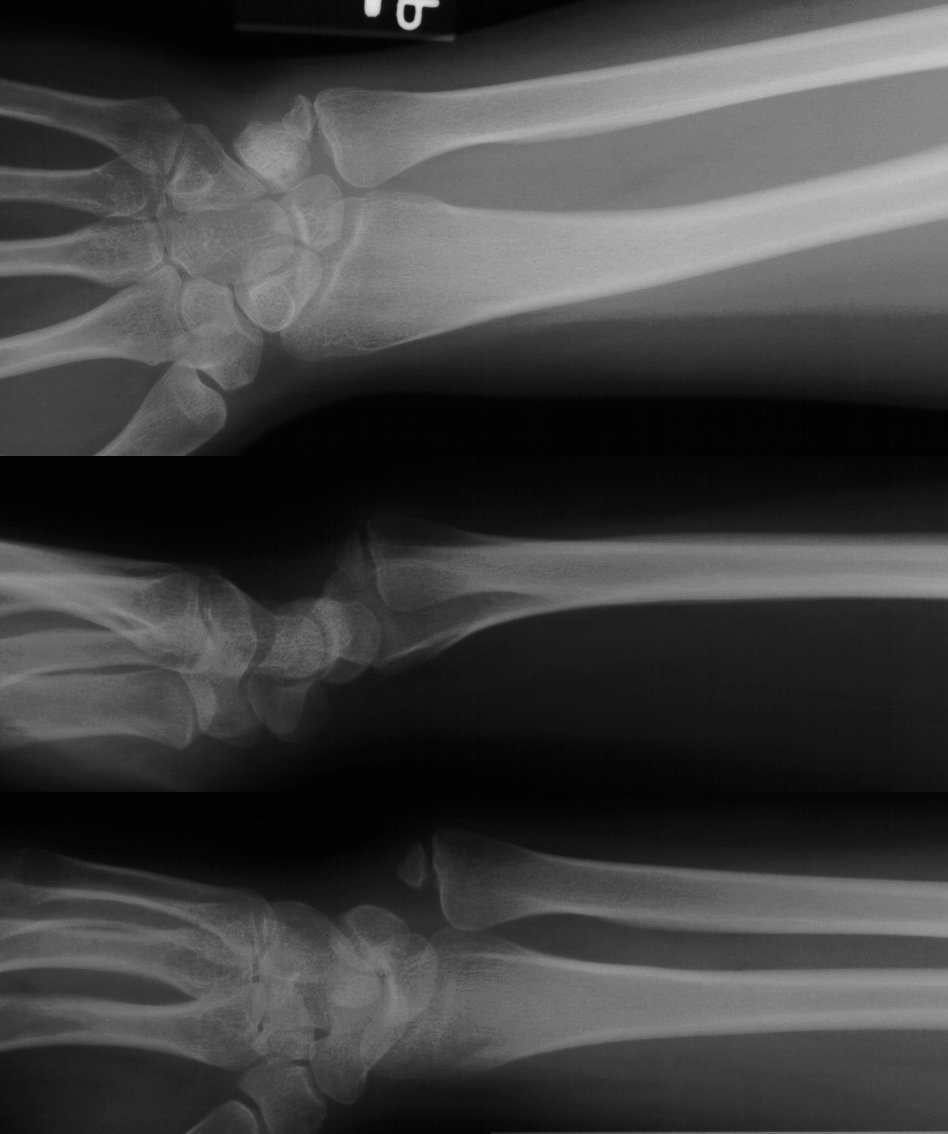

Case 2. Minimal Madelungs picture following pediatric distal radius fracture.